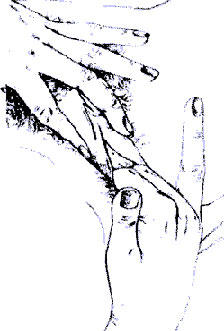

Осторожно раздвиньте внутренние половые губы, чтобы открыть вход во влагалище. Если они достаточно увлажнены, вы можете ввести во влагалище один или несколько пальцев без неприятного ощущения. Изучите различия в чувствительности влагалища. Вход и нижняя часть обычно более чувствительны, чем внутренняя часть влагалища.

· Затем так же тщательно, как при осмотре, исследуйте ваши половые органы руками. Не переходите к этой фазе, пока не станете смотреть на половые органы совсем спокойно. Нет нужды спешить с этим, если исследование руками кажется вам затруднительным. Важно повторять его хотя бы урывками, но как можно чаще.

· Обведите пальцами вдоль малых и больших губ и вдоль промежности (область между влагалищем и задним проходом), чтобы определить наиболее чувствительные участки.

· Исследуйте пальцами вход во влагалище, для чего раздвиньте малые губы, открыв вход. Область вокруг входа и наружная треть влагалища более чувствительны к прикосновению, чем внутренние две трети, которые реагируют только на давление.